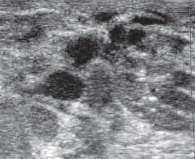

Опухоли подразделяют на доброкачественные и злокачественные [1, 5]. У девочек наиболее распространена ювенильная фиброаденома – доброкачественная фиброэпителиальная опухоль, обычно возникающая в пубертате и склонная к быстрому росту (рис. 2) [5, 11, 12]. Чаще это одиночный узел. Множественные очаги отмечают примерно у каждой пятой пациентки, двусторонние – примерно у каждой десятой [5, 12, 13].

На УЗ-картине солидное, гипоэхогенное по сравнению с тканью МЖ образование однородной структуры, с четкими контурами. Нередко наблюдается дорсальное псевдоусиление без акустической тени (рис. 3–5) [5, 7, 10].